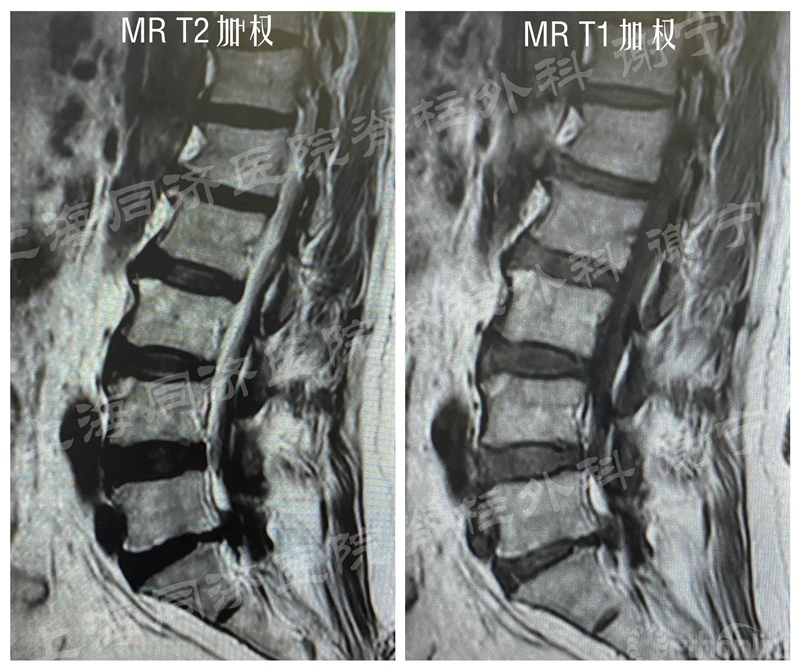

患者男性,66岁,左下肢疼痛麻木2月余,加重3周入院。左直腿抬高征阳性。X线片示腰椎轻度侧弯,未见明显不稳。MR和CT示L5/S1椎间盘脱出,椎间盘合并骨化,中央偏左侧。

图12 MR加权